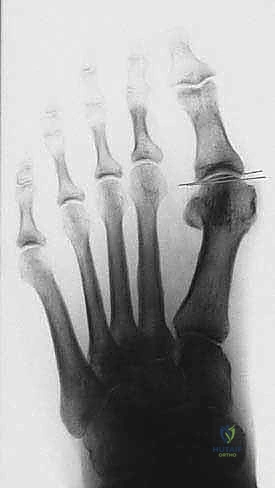

- التصوير بالأشعة السينية (X-rays) أثناء الوقوف: هذا أمر بالغ الأهمية. الأشعة والوزن محمل على القدم تظهر الدرجة الحقيقية للتشوه.

يقوم الدكتور هطيف بقياس زوايا محددة:

* زاوية إبهام القدم الأروح (HVA): الزاوية بين عظم المشط الأول والإصبع الكبير.

* الزاوية بين الأمشاط (IMA): الزاوية بين عظم المشط الأول والثاني.

بناءً على هذه الزوايا، يتم تصنيف الحالة إلى خفيفة، متوسطة، أو شديدة. جراحة (ماو) تُخصص عادة للحالات المتوسطة إلى الشديدة التي تتطلب تصحيحاً كبيراً ومستقراً.

الخطوة الرابعة: إعادة التوجيه والتثبيت الداخلي

بعد قص العظم، يتم تحريك الجزء البعيد (الذي يحمل المفصل والإصبع) نحو الخارج لتصحيح التشوه وتضييق المسافة بين الأمشاط. بمجرد الوصول للوضع المثالي، يتم تثبيت العظمين معاً بقوة باستخدام برغيين أو ثلاثة من التيتانيوم الطبي عالي الجودة. هذه البراغي تدفن داخل العظم ولا تحتاج للإزالة لاحقاً.